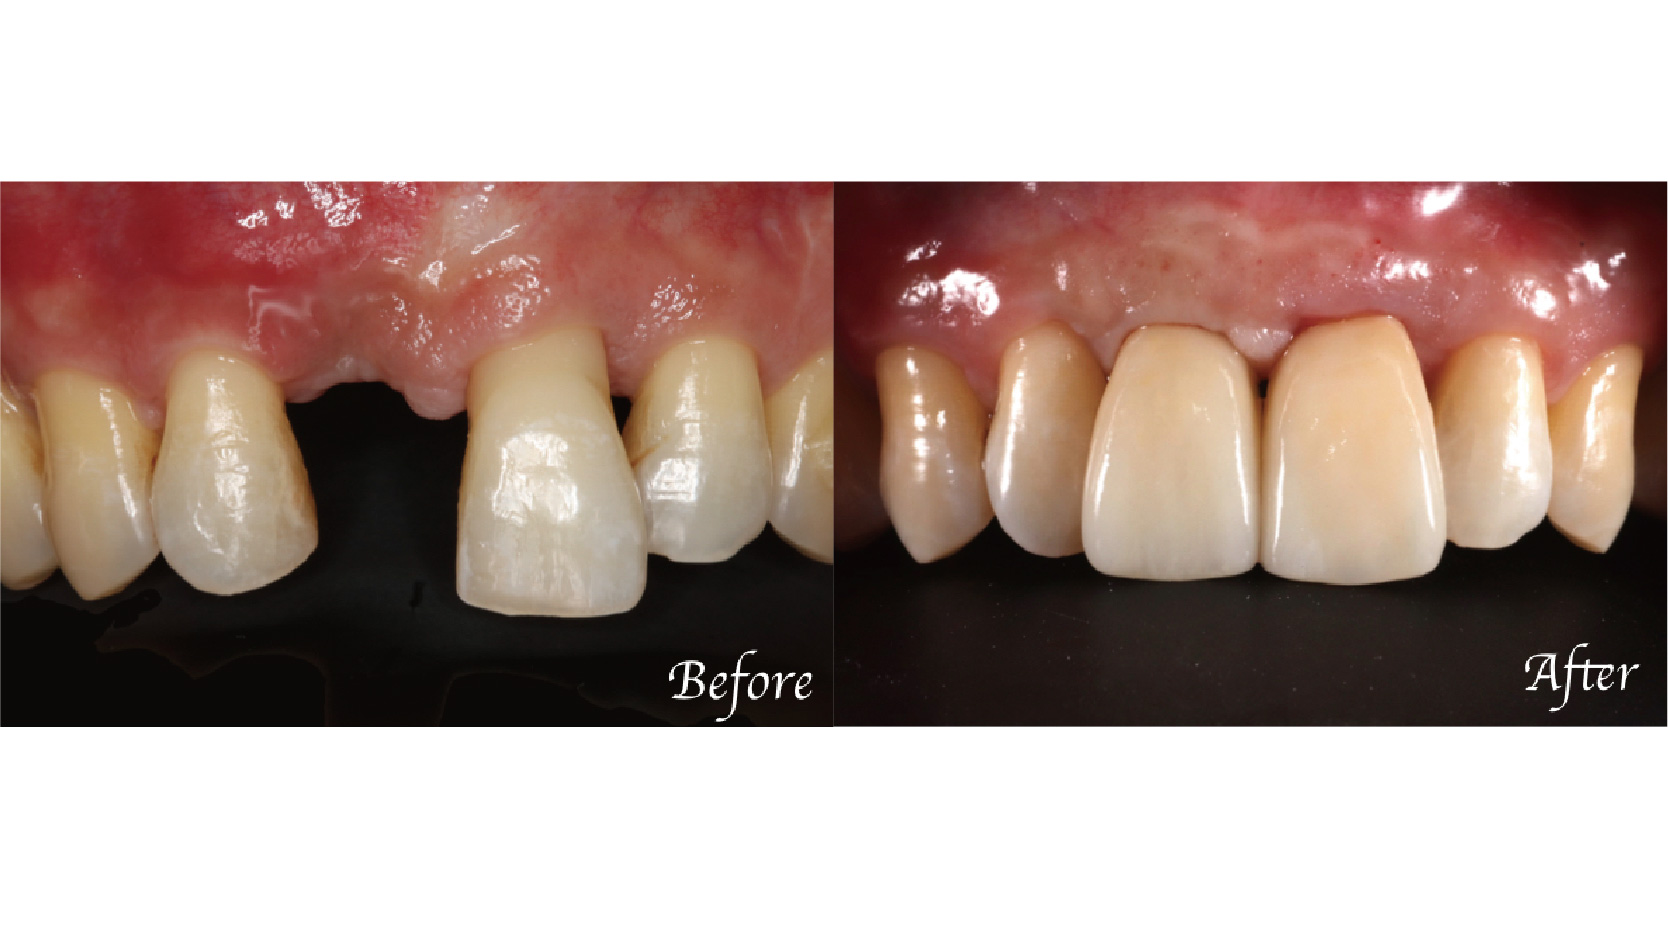

牙周病美學植牙|副院長 林國義 醫師